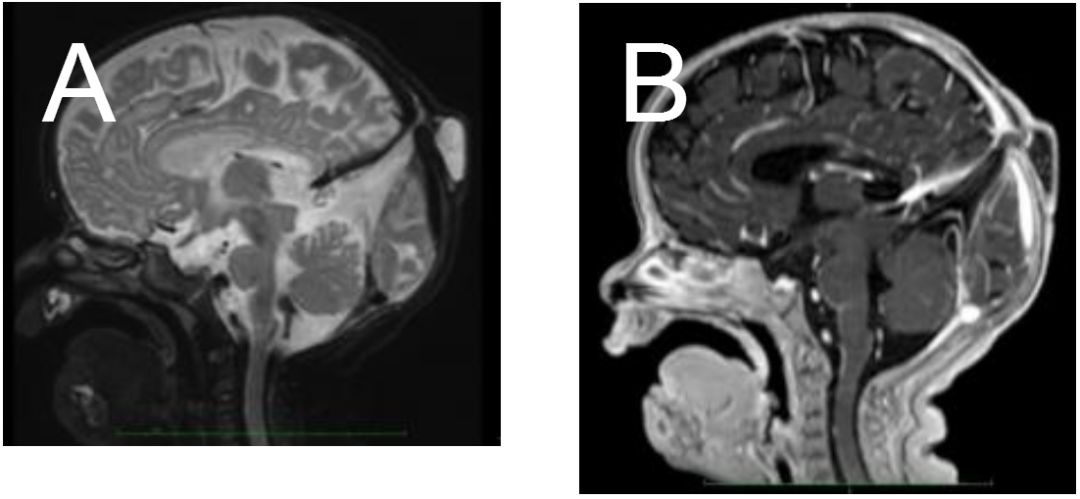

两岁女孩,有一可触及的中线顶骨软组织无痛性肿块。发育正常,神经学检查未见明显异常。影像学如下:

正中矢状面T2 (A)和3D增强T1 (B)提示一颗颅底软组织肿块(白色箭头),并通过边界清楚的骨缺损(星号)伴随脑脊液信号与颅内沟通。下矢状窦持续存在(等同于直穿静脉窦,黄色箭头)、上矢状窦局灶不连续性(星号)。小脑上池突出也可观察到小脑幕高异常嵌入(蓝色箭头)。